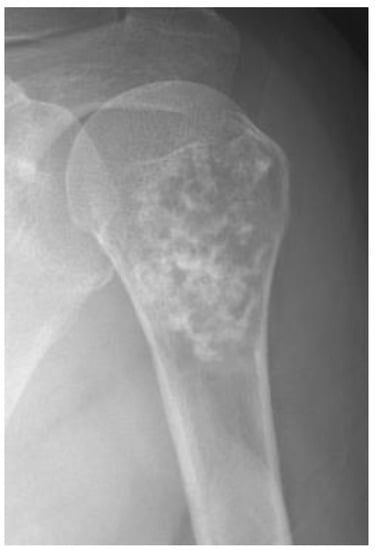

3.1. Distinction between Enchondroma and ACT

3.3. Distinction between ACT/CS1 and High-Grade Chondrosarcoma